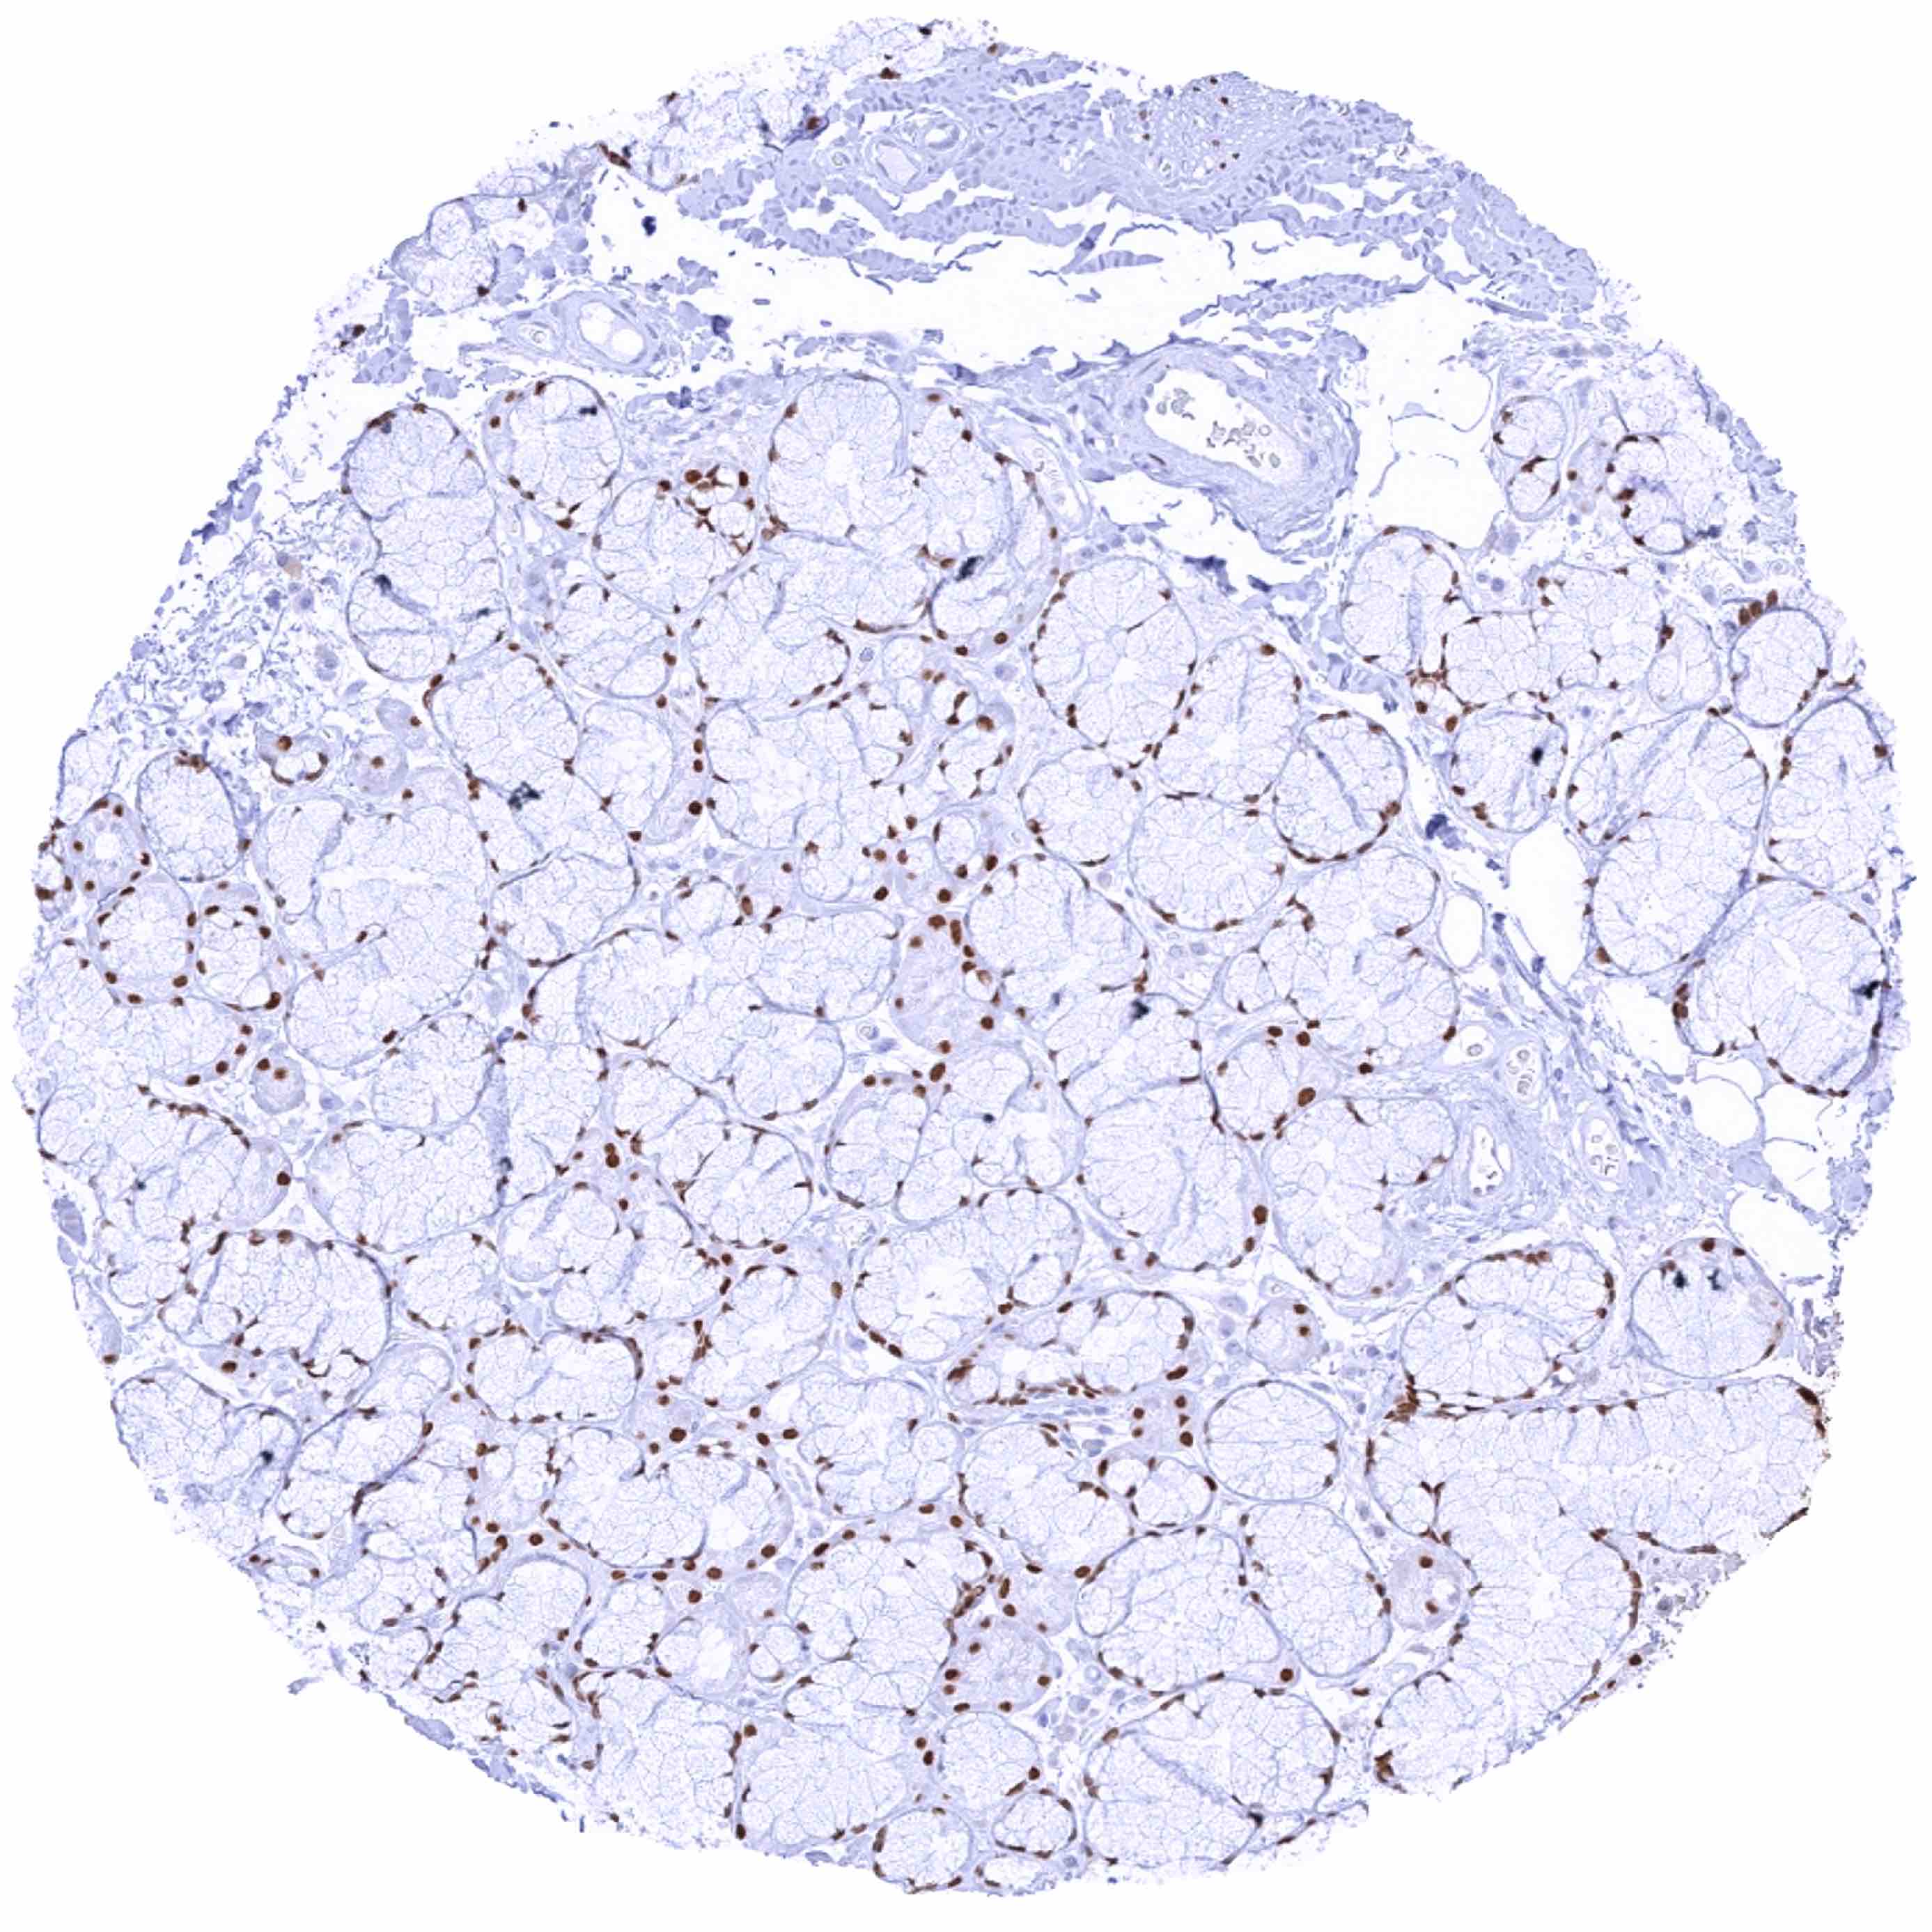

Prostate – Strong SOX2 positivity of a fraction of basal cells